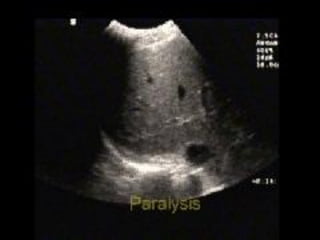

Absent lung sliding

Exaggerated horizontal artifacts

Loss of comet-tail artifacts

Broadening of the pleural line to a band

The key sonographic signs of

Pneumothorax

Absent lung sliding Exaggeratedhorizontal artifacts Loss of comet-tail artifacts Broadening of the pleural line to a band The key sonographic signs of Pneumothorax